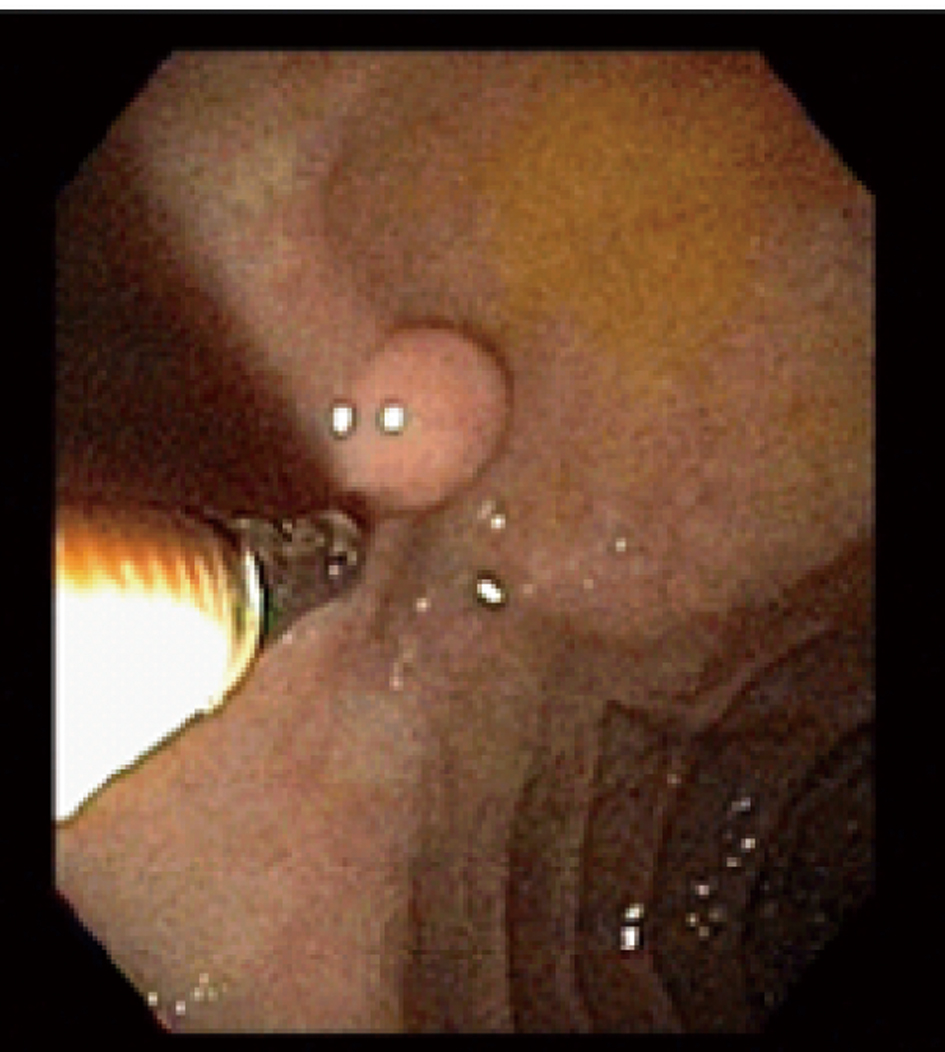

A 59-year-old male with a past medical history of hepatitis C and hypertension presented complaining of worsening abdominal pain associated with bright red blood per rectum for the past month. The pain was 7/10 in intensity, constant, non-radiating, with no alleviating or aggravating factors. He admits having 2 - 3 episodes of bloody stools per week. He also reported a 20 pounds weight loss in the last 6 months. Review of systems was otherwise negative. Social history was significant for a 15 pack year history. He denied family history gastrointestinal malignancies. Vitals on admission were within normal limits. Physical exam was significant for right upper quadrant tenderness without guarding, rebound, or organomegaly. Rectal exam revealed no blood or masses. Laboratory results showed iron deficiency anemia with hemoglobin of 9.6 K/mm3. Liver related tests and coagulation profile were within normal limits. Esophagogastroduodenoscopy revealed a 4mm duodenal polyp (Fig. 1). Colonoscopy was terminated early secondary to a large circumferential obstructing mass (Fig. 2) found in the descending colon. Immunohistochemistry of the duodenal biopsy was positive for synaptophysin and chromogranin-A (Fig. 3); consistent with the diagnosis of stage I carcinoid tumor. Biopsy results of the colonic mass showed a stage I well-differentiated adenocarcinoma (Fig. 4). The patient underwent a left colectomy and partial duodenectomy. He remains in remission after 2 year of close follow up.

![]() Click for large image | Figure 1. A 4 mm duodenal polyp found during endoscopy. |